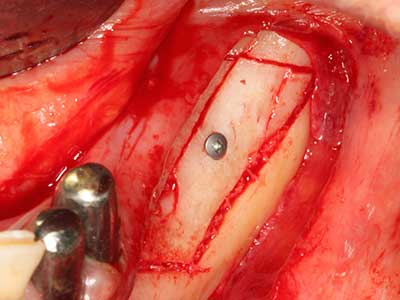

Para la extracción de implantes es posible realizar la preparación de una tapa ósea vestibular que, tras retirar el tornillo del implante, vuelve a fijarse y, de este modo, mantiene el contorno de la apófisis alveolar.

En la cirugía del seno maxilar surgen otros campos de aplicación: En este punto, tras la preparación concéntrica de una tapa ósea de la pared del seno maxilar (que suele tener forma trapezoidal), es posible eliminar patologías y cuerpos extraños del seno maxilar. La tapa ósea se repone después de finalizar la parte intra-antral de la operación y se asegura frente a una posible dislocación mediante cuñas o suturas adaptables.